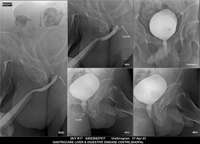

Section: URETHROGRAM

Total: 95 Cases

All Categories BaM Enteroclysis Loopogram BaE Fistulogram Urethrogram HSG